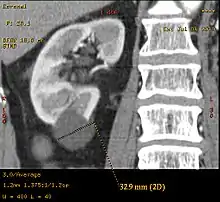

Renal cyst of the left kidney (hyperintense area) as shown on MRI. | |